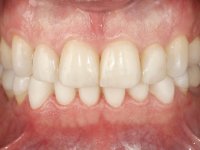

Após análise clínica e imagiológica foi proposto ao paciente recuperar a dimensão vertical da oclusão essencialmente à custa de incrementos oclusais inferiores utilizando “overlays” no sector posterior e facetas no sector anterior. A coroa aparafusada sobre o implante 3.5 seria substituída, no sentido de acompanhar este incremento. Na maxila o dente 2.6 teria extração indicada e posteriormente seria reabilitado com um implante e respetiva coroa. No sentido de reabilitar esteticamente o paciente duma forma minimamente invasiva, foi proposta a colocação de facetas feldespáticas no sector antero-superior. O objetivo de aumentar ligeiramente a D.V.O., teria como função “proteger” eficazmente o sector antero-superior.

Realizado o diagnóstico e tomada a decisão quanto ao tratamento a executar, tornou-se importante definir qual a sequência de trabalho a adotar no sentido de conseguir a reabilitação da D.V.O. (V.D.O), de forma progressiva e equilibrada. Na primeira fase fez-se uma pré-impressão da arcada inferior com silicone tipo “putty” e em seguida realizou-se o preparo dentário de todo o sector posterior. O preparo para os overlays foi feito coronalmente à linha amelo cementaria no sentido de ser o mais conservador possível. A impressão foi feita com técnica de dupla mistura após afastamento gengival realizado com pasta de caulino. A provisória foi realizada com resina composta de polimerização dual. Em laboratório foram realizados os overlays após se ter aberto ligeiramente (1,5mm) a D.V.O. nos modelos montados em articulador semi-ajustável. Simultaneamente o sector antero-inferior foi encerado no sentido de acompanhar este aumento da D.V.O. Também foi confecionada uma chave de silicone translucido para posterior confeção dos provisórios antero-inferiores. Em boca foi primeiro realizada a provisionalização dos dentes anteriores utilizando resina composta previamente aquecida após preparação das superfícies dentárias para a adesão. Foi colocado o dique de borracha para promover o isolamento absoluto e posteriormente foram colados os overlays. Em laboratório foi realizada nova chave de silicone para confecionar os provisórios antero-superiores. Seguidamente em boca foram preparados os seis dentes antero-superiores após colocação do fio de afastamento gengival. Feita a preparação adequada das superfícies dentárias foi realizada a impressão com técnica de dupla mistura e a respetiva provisória. Em laboratório foram confecionadas 6 facetas feldespáticas num modelo de trabalho tipo “Geller”. A provisória foi removida e as facetas foram coladas em boca utilizando um isolamento relativo competente. Esta opção foi tomada em virtude de uma prévia experiencia negativa com a colocação do dique de borracha na mandibula. Após a colagem dos laminados antero-superiores foram dadas 12 semanas para avaliar a adaptação do paciente à nova situação e então iniciar a confeção das facetas antero-inferiores. Após colocação do fio de afastamento gengival. foram feitos os preparos dentários adequados e em seguida foi feita a impressão. Também foi feita a preparação do dente 3.4 que, entretanto, tinha sofrido uma fratura do overlay. As facetas e a restauração do 3.4 foram realizadas num modelo de trabalho tipo “Geller”. Após remoção da provisória, as facetas foram coladas em boca, utilizando um isolamento relativo pelas razões apontadas anteriormente. Após colocação do trabalho o paciente foi reabilitado por outros colegas com um implante na zona do 2.6 e substituição da coroa aparafusada sobre o implante colocado no local do 3.5. Posteriormente surgiram fraturas nos overlays dos dentes 4.7 e 3.7 que foram reabilitados com overlays em Zr.